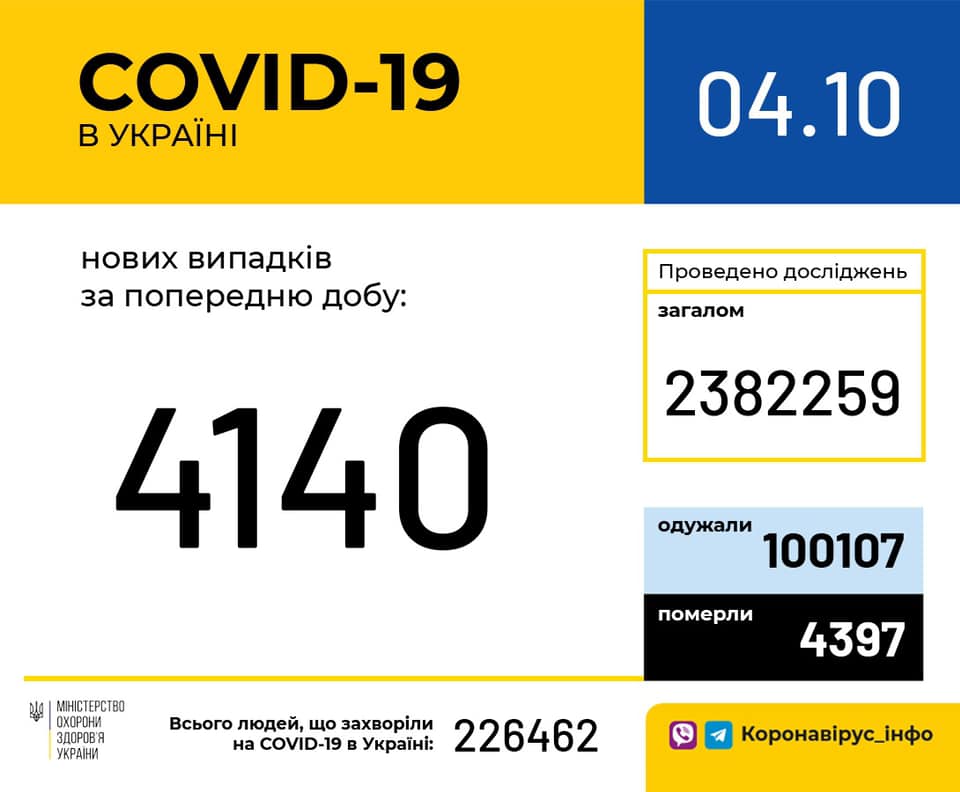

Більше 3 тисяч випадків захворювання на коронавірус зафіксували в Україні за добу

11.09.2020 09:37